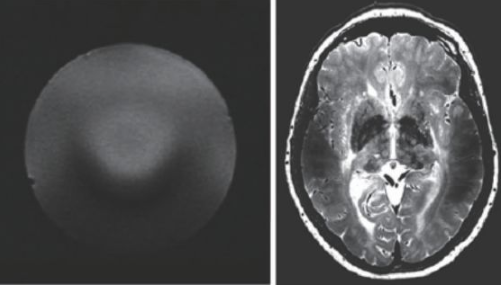

超高场MRI的射频场设计也是一个较为困难的问题。由于射频频率超过了300 MHz,介电常数引起的问题非常突出。图13 是一个在7 T 下的成像结果,可以看到在图像内部的信号非常不均匀,由于射频波长的极度缩短,组织的介电常数对射频场的分布有极大的影响,这也是目前超高场MRI 需要解决的重要问题之一。目前的9.4 T以上的MRI设备还难以获得人体体部扫描的良好图像,其主要应用还是做头部的扫描。

图13 超高场下的射频场不均匀性